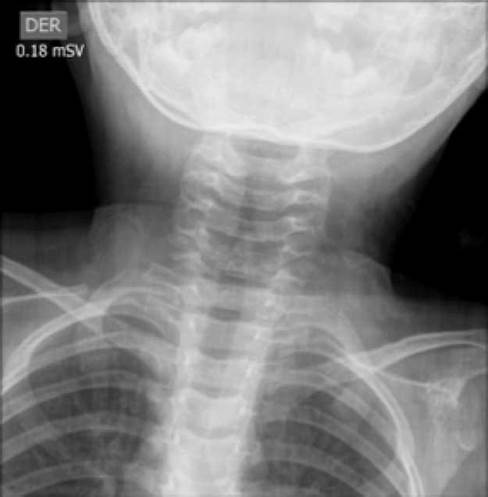

Chest and neck radiographs were requested for an initial approach (Figure 1 and 2). The radiology service found a steeple sign that suggested laryngeal croup in the anteroposterior (AP) projection of the second image. Likewise, the lateral projection shows an object that could be a foreign body. Chest X-ray was normal.